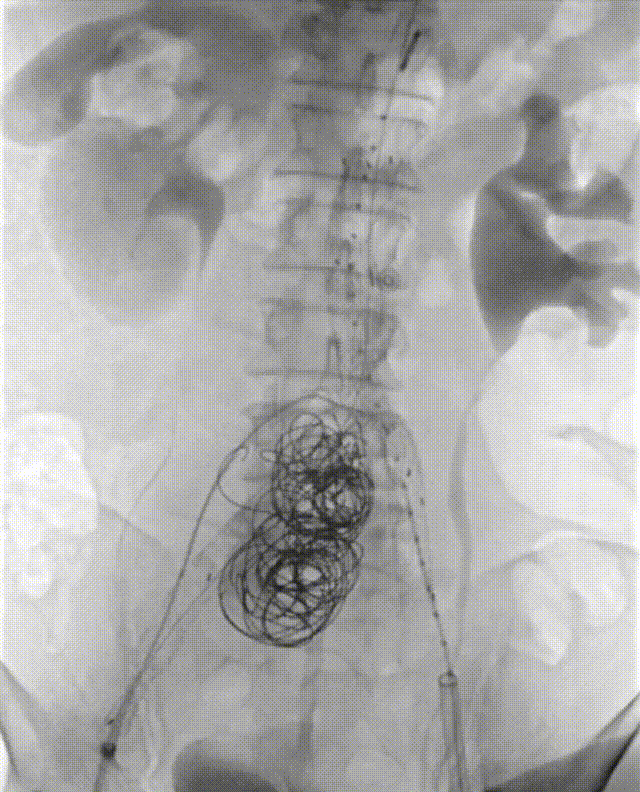

16. 因为髂总瘤腔巨大以及右侧髂内未进行栓塞,稳妥起见,经预留导管对右侧髂总进行弹簧圈填塞。

gore医疗怎么样「漫腹精论」髂合时宜 精益求精——双MOB球囊导管辅助腹主动脉覆膜支架急诊治疗破裂巨大髂动脉瘤_https://www.jmylbn.com_新闻资讯_第25张

17. 后扩后再次进行造影,瘤体未见显影,双侧肾动脉,左侧髂内动脉,双侧髂外动脉通畅,结束手术。